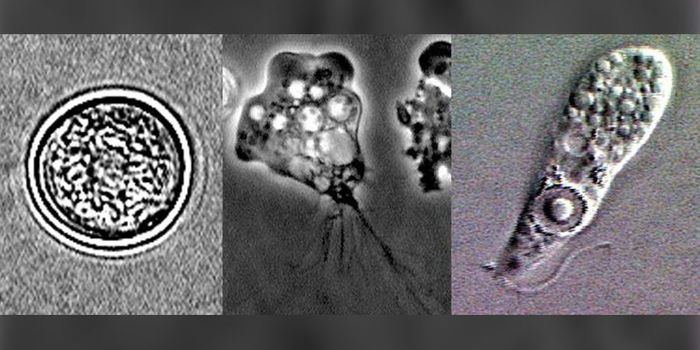

FEB 21, 2016Clinical & Molecular DXA staggering 30-50% of the world’s population is estimated to be infected with the parasite Toxoplasma gondii. Thi ...

AUG 22, 2016Clinical & Molecular DXSummer is prime time for activities on the river. But a swim in the river turned into a life-threatening event for a Flo ...